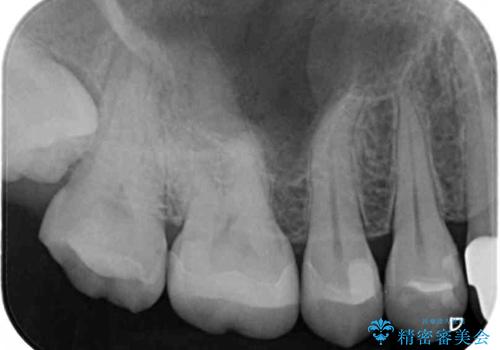

- 他院で治療を開始したものの抜歯が必要と言われ、何とか残せないものかとのことで来院された患者様です。

下顎大臼歯は歯冠部分が残っておらず、保存が難しいように思えましたが、まずは根管治療を行った上で補綴治療を行うこととしました。

上顎臼歯は、おそらく銀歯を外して仮詰めされていたため、再度形を整え、セラミックインレーにて修復治療を行うこととしました。